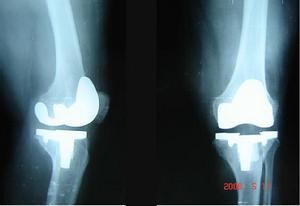

(十一)手術治療 急性關節炎嚴重疼痛,局部有滲液時可抽降滲液,並注入類固醇抗炎藥,再使用夾板固定關節。腕及足下垂時可夾板固定及理療。持續性滑膜炎可考慮行滑膜切除術。肌腱破裂及神經受壓迫者應考慮手術治療。後期關節畸形及嚴重障礙者也可手術治療,如關節成形術、關節固定術、截骨術、人工關節置換術及伸側肌腱重建術等。